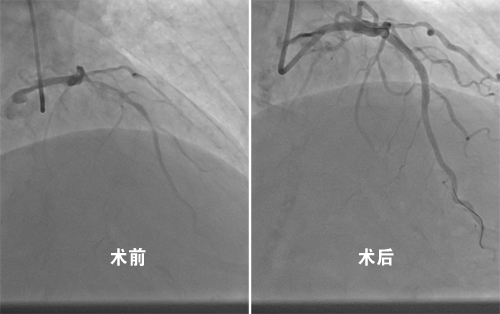

12月26日,临床医学院/附属医院心血管内科黄问银团队首次运用刚引进的血管内超声诊断仪(intravenous ultrasound,IVUS)和冠状动脉内膜旋磨技术(eoronary trartsluminal rotational atherectomy,Rotablator),成功地为一位冠脉严重钙化伴狭窄的78岁男性患者,完成了一台高难度的冠脉支架植入手术。手术历时1个多小时,有效地解决了患者多年心绞痛症状,避免了因血管钙化导致的术中风险和操作难度。

冠脉旋磨技术是利用高速旋转的旋磨头对球囊无法扩张的内膜纤维化、钙化病变进行介入治疗的技术,被称为“血管内行走的金刚钻”。冠脉旋磨技术,使得包括左主干病变、分叉病变、严重钙化、慢性闭塞等以往常规手段无法干预的复杂病变的治疗成为可能。